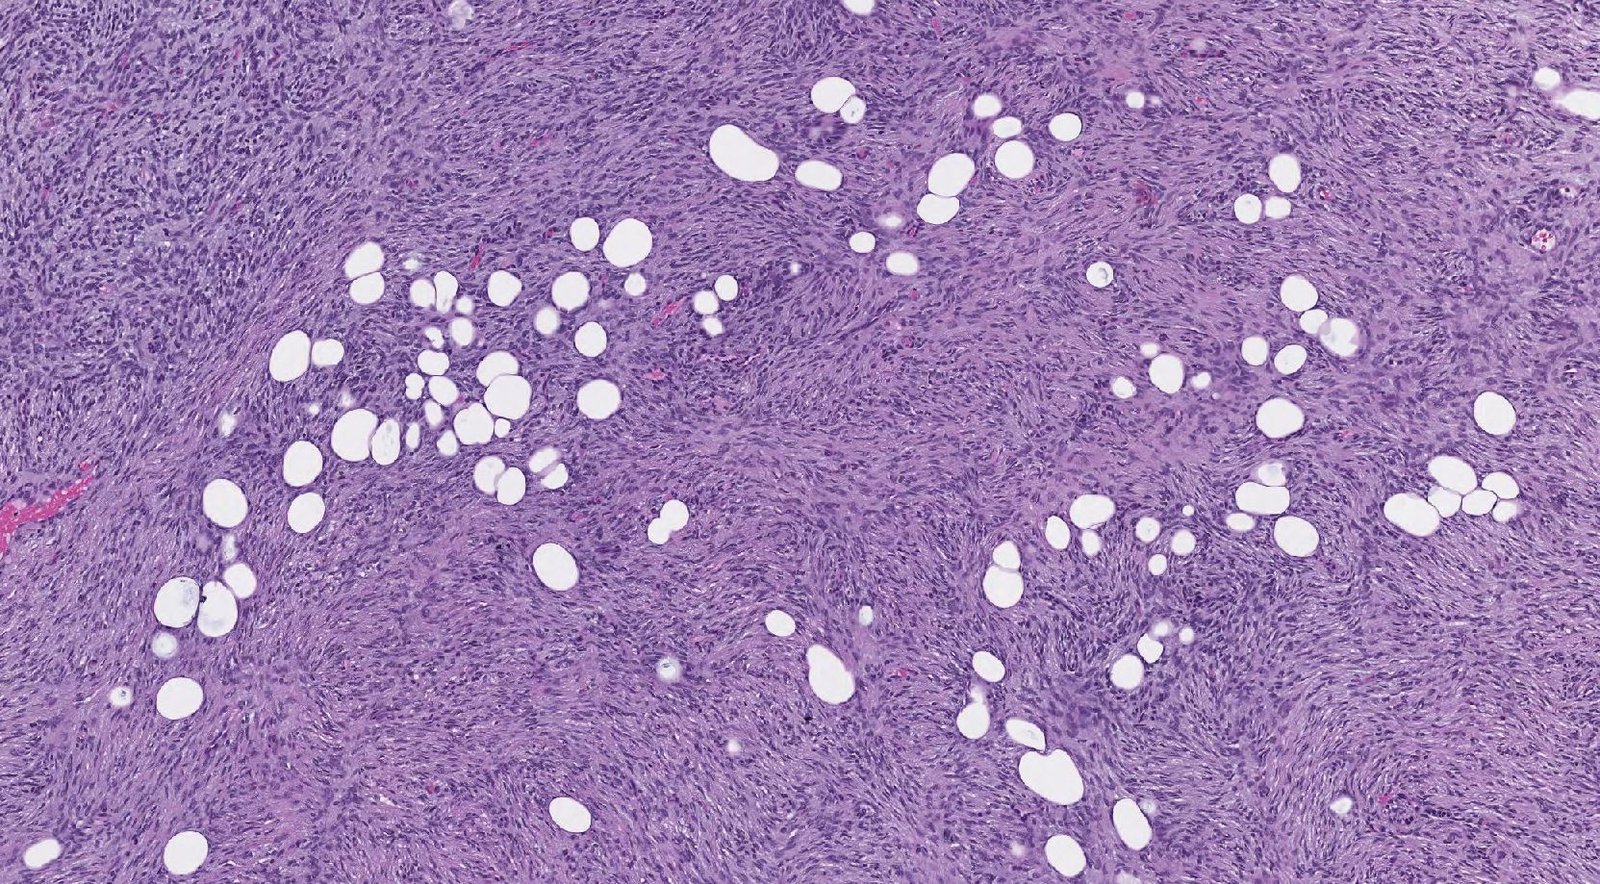

Case: SkinNodule

Final Diagnosis: